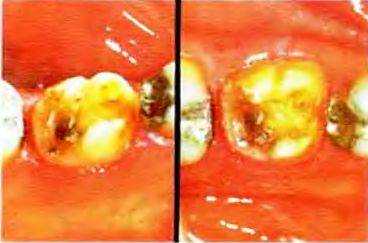

Рис. 16-33а, Ь. Перелом дистального язычного бугорка моляра нижней челюсти. Решено изготовить полную коронку по причине декальцинирования и кариозного поражения осевых поверхностей. На дистальнои поверхности сформирована большая четкая коробчатая полость с перешейком, переходящим на медиальную поверхность

Рис. 16-33а. Внешний вид зуба с язычной (слева) и окклюзионной (справа) поверхностей